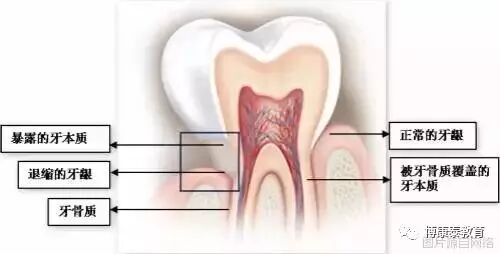

谈到洗牙,大多数人关心的问题,确实是牙齿酸软。很多洗过牙的人会在最初几天,感觉牙齿非常敏感,遇到冷热酸甜会牙齿酸软,这叫做牙本质敏感,是洗牙以后常见的一种症状。

原因很简单,原来牙齿有藏污纳垢的牙石包裹,牙龈经常发炎、出血,牙骨质也可能被破坏了;洗掉牙石后,牙齿恢复原貌,但由于牙龈退缩,导致牙根位置的牙本质暴露,一碰到冷热酸甜,就会让人酸软不适。

图2 牙石覆盖的牙齿

图3 方框内显示牙龈退缩、牙骨质破坏后暴露的牙本质